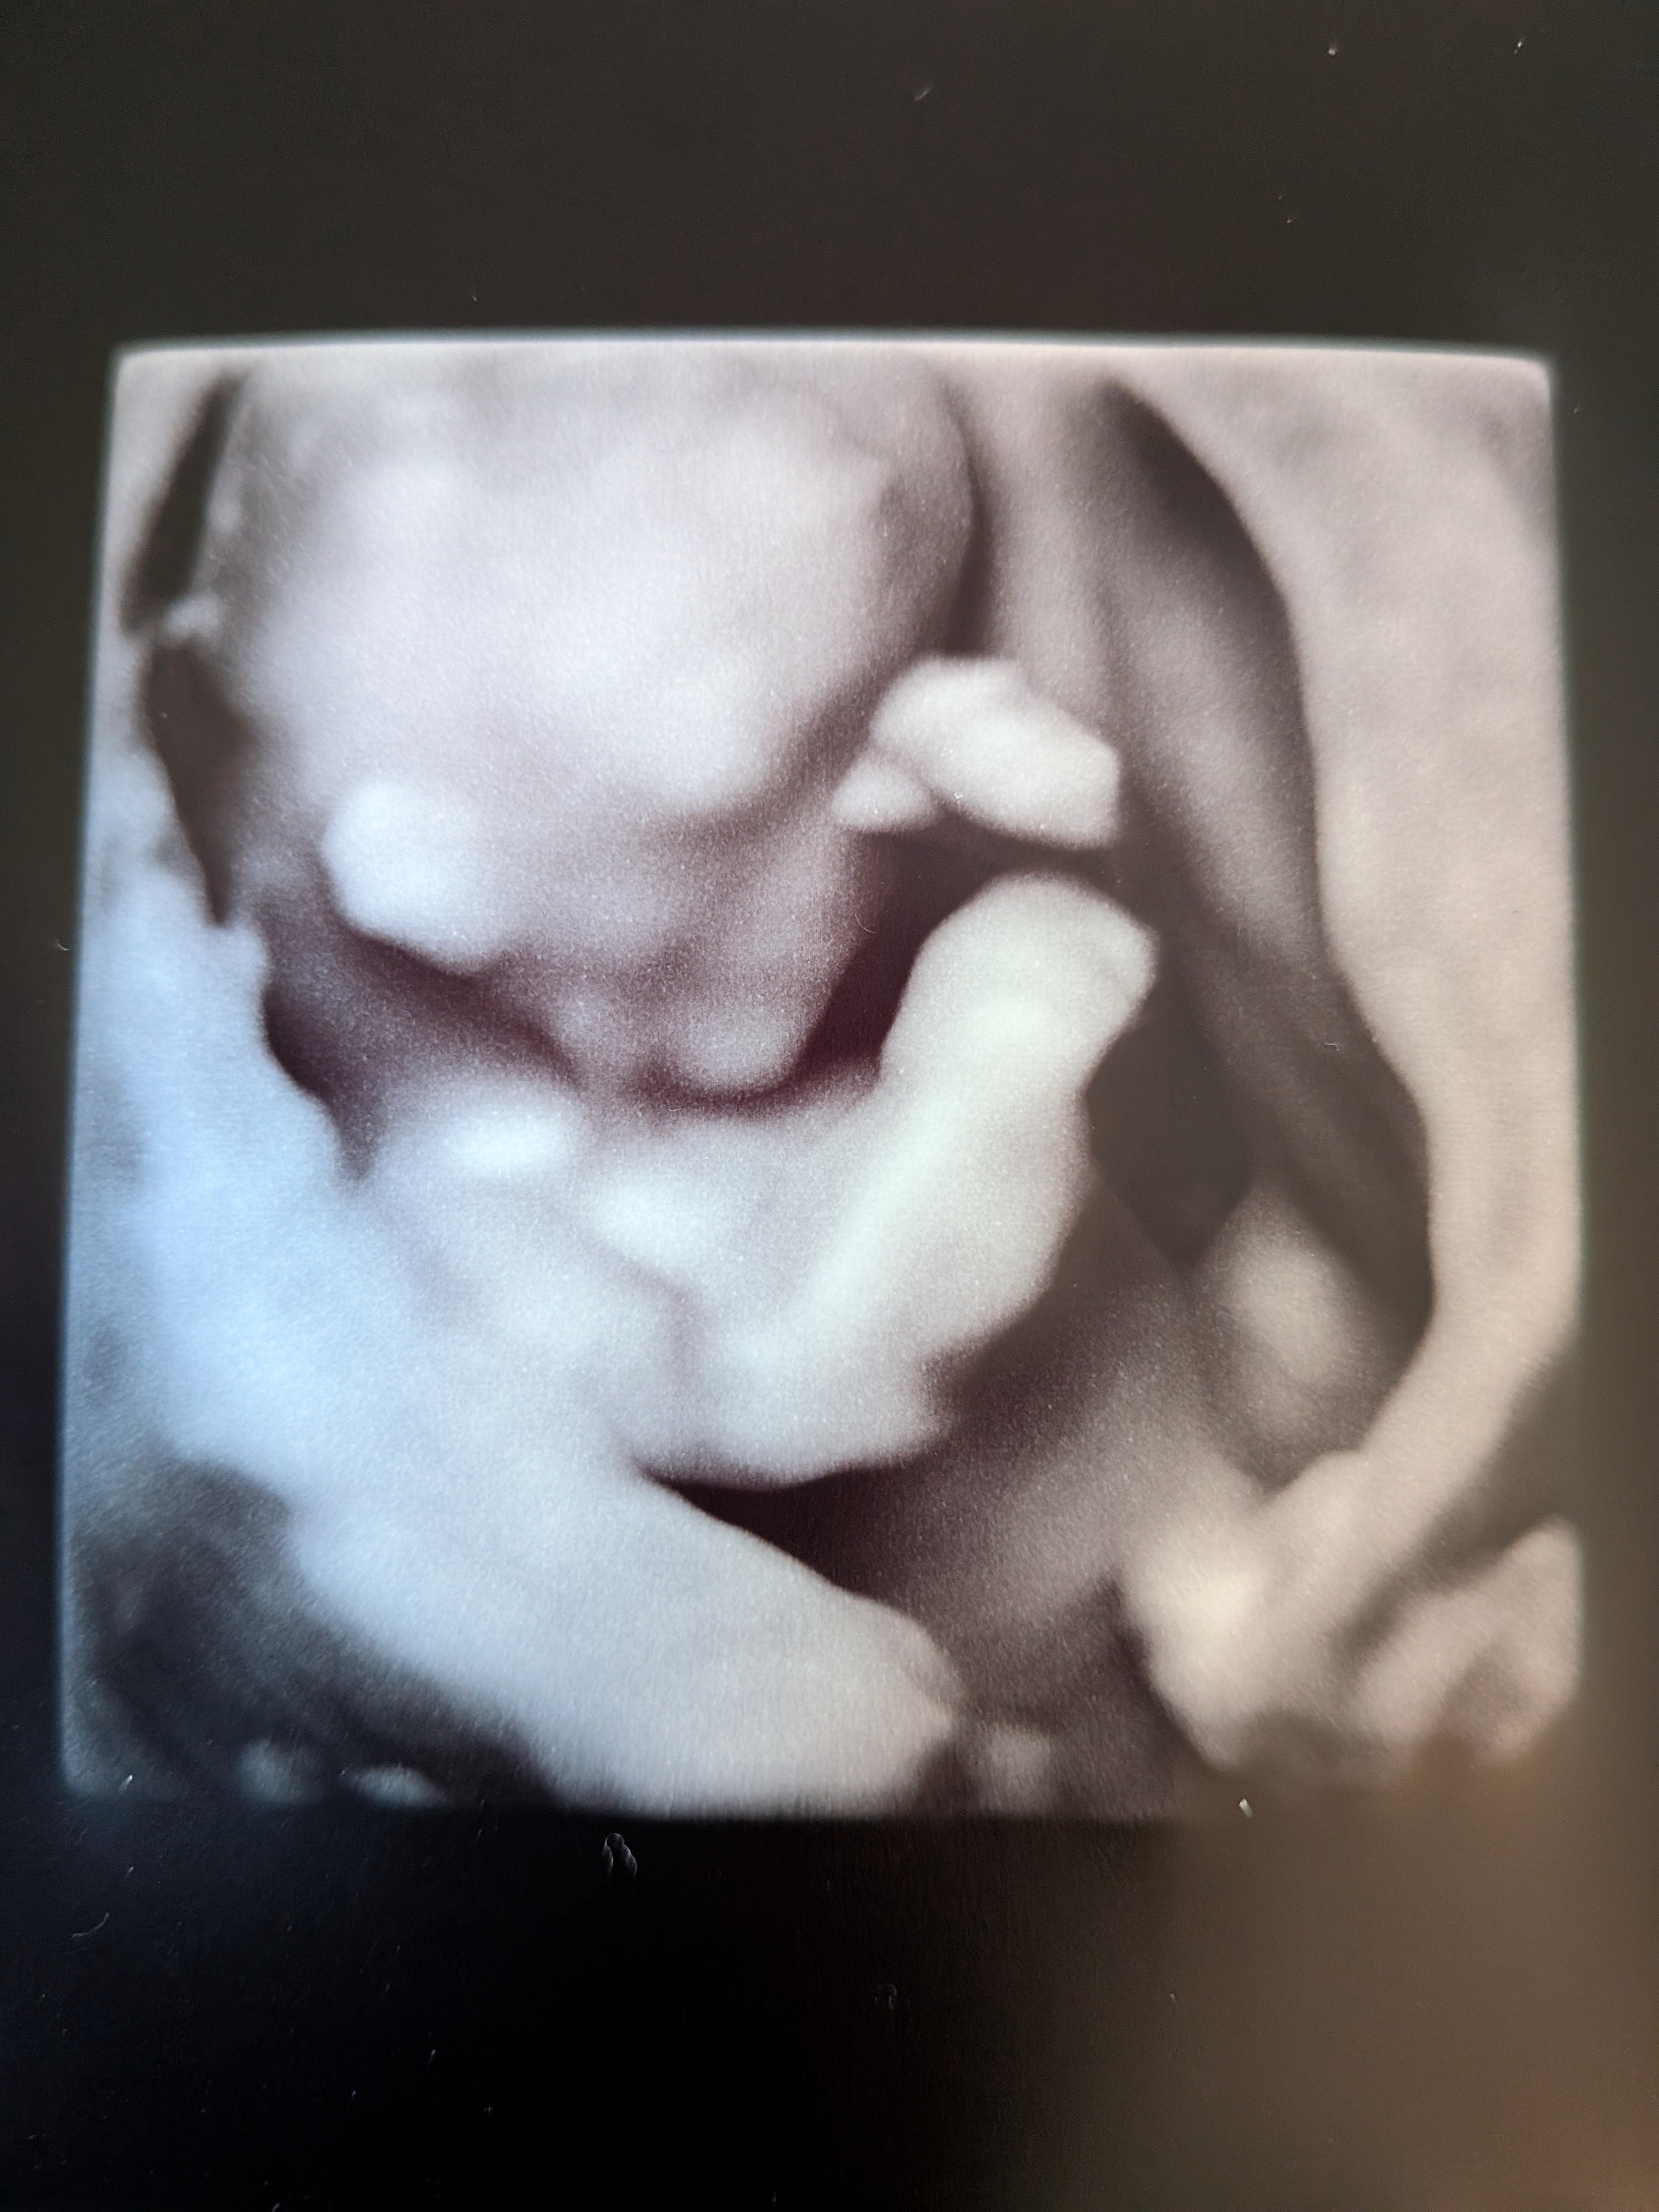

Mannen tenkte feil (selv om han sa kl høyt) og vi endte opp på sykehuset 1 t før OTUL. Utforsket bygget imens. Plutselig fikk jeg sms om at det var min tur! :oops: Viste seg at hun som hadde timen før meg satt fast i kø, så da fikk jeg hennes. Flaks da! Rakk såvidt å bli nervøs. Pratet litt før timen, om forrige fødsel og evt. oppfølging nå, får vite mer om det på OUL. Før vi begynte var hun veldig klar på at man ikke får vite kjønn. Vi sa det går heelt fint, vi er ikke opptatt av det. Jeg syns egentlig folk er litt for opptatt av kjønn :bag: Det syns hun var forfriskende! Også sa hun "eg seie alltid han pga. dialekt". Vi snakket litt videre om datteren vår ila. timen, og etterhvert begynner hun å si "ho" - hun skyldte fort på at det var pga. vi har jente fra før, men lurer på om hun forsnakket seg der :p Anyway, vi så med én gang at det var en frisk og superaktiv krabat inni der! Den hoppet og turnet og snurret rundt - med boksenever foran ansiktet :laughing002 Skulle ikke drukket de slurkene med red bull, for det var vanskelig å få målt :smiley-ashamed004 Men det gikk etterhvert, fikk akkurat nakkefolden til slutt. Ble mange bilder også, inkl. i 3D! Alt så veldig bra ut. Så ingen nub, men jeg kan ikke de greiene uansett. Men basert på at jeg ikke så en penis og en potensiell forsnakkelse lurer jeg på om det blir ei jente til :joyful: Jeg hadde jo egentlig lyst på gutt, men kjenner ikke på noen skuffelse der, selv om det ikke er sikkert ennå. Holder forresten mistanken min privat, for kjente jeg ble litt irritert at alle drev og spurte etter kjønnet etter jeg snappet om vellykket UL :rolleyes: Det er ikke viktig! Senere gikk jeg forbi en Brando Kids og fant ei kasse med ull til 50%, så kjøpte noen plagg i 50-56 :D Det var for det meste "jentefarger" men det driter jeg i :wacky: Fikk btw OUL den 17.09. (18+2)!